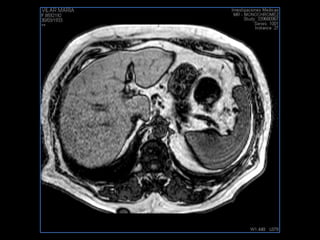

LIC ALEJANDRA GALVEZ RM DE ABDOMEN

PROTOCOLO abdomen COR T2, AXIAL supresion grasa AX T1 +SAG T2  CON   GADOLINIO :  COR T1+AX T1(DIN) SAT: NO  FASE: RL THK: 6MM  COIL:  GAP: (FACTOR 1.4) 2MM FOV: 40 CM NEX:2 SINCRONIZACION RESPIRATORIA EN 3 O 4 CICLOS ALE

PROTOCOLO hígado graso AXIAL in phase y out phase AX T1 y AX fat sat +SAG T2  CON   GADOLINIO :  COR T1+AX T1(DIN) SAT: NO  FASE: RL THK: 4MM  COIL:  GAP: (FACTOR 1.4)  FOV: 40 CM NEX:2 SINCRONIZACION RESPIRATORIA EN 3 O 4 CICLOS ALE

PROTOCOLO hemocromatosis AXIAL supresión grasa /AX multieco en higado COR T2 AX T1 +SAG T2  CON   GADOLINIO :  COR T1+AX T1 SAT: NO  FASE: RL THK: 4MM  COIL:  GAP: (FACTOR 1.4) 1MM FOV: 40 CM NEX:2 SINCRONIZACION RESPIRATORIA EN 3 O 4 CICLOS ALE

PROTOCOLO pancreas/ riñon AXIAL fat sat /AX in phase out phase AX T1 +SAG T2  COR T2, CON   GADOLINIO :  COR T1+AX T1(DIN) SAT: NO  FASE: RL THK: 4MM  COIL:  GAP: (FACTOR 1.4) 1MM FOV: 40 CM NEX:2 SINCRONIZACION RESPIRATORIA EN 3 O 4 CICLOS ALE

resonancia de abdomen